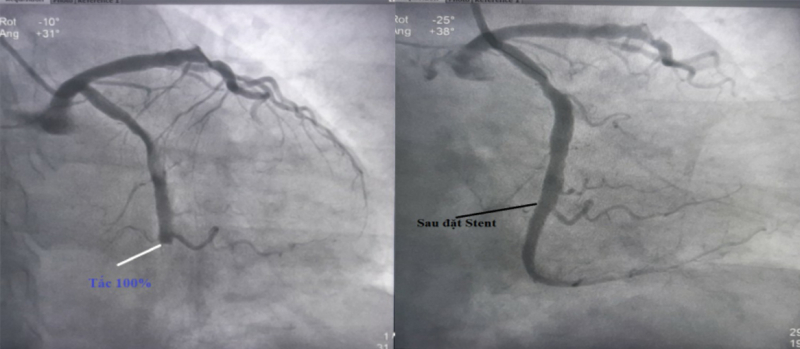

Ngay lập tức, bệnh nhân được đưa lên phòng can thiệp mạch DSA. Hình ảnh chụp mành vành xác định bệnh nhân bị tắc hoàn toàn đầu đoạn 2 động mạch mũ, hẹp 60% động mạch liên thất trước, xơ vữa động mạch vành phải. Ekip can thiệp của Thạc sĩ, bác sĩ Trần Văn Quý, Đinh Danh Trình – Khoa Tim mạch, Bệnh viện Bãi Cháy đã tái thông và đặt stent phủ thuốc vào đoạn mạch bị tắc. Ngay sau can thiệp, bệnh nhân đỡ đau ngực, thoát nguy kịch, chỉ số sinh tồn ổn định.

Đoạn động mạch bị tắc trước can thiệp (bên trái ) và được tái thông sau can thiệp (bên phải)